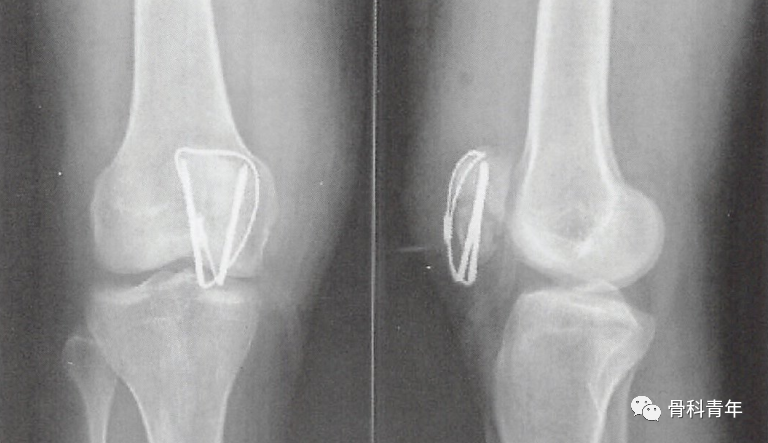

2.张力带固定

张力带固定是髌骨骨折最主流的固定方法,通过将前方的张力转变为骨折块间压力。具体步骤如下图所示:

有学者进行生物力学发现,在膝关节屈曲时,关节面压力并未增加,但在膝关节屈曲时关节面会产生裂隙。因此把克氏针固定认为是“静态加压”,而非“动态加压”。克氏针的置入位置,在矢状面上应位于髌骨后1/3,才能达到良好的张力带作用。

与克氏针张力带相比,采用空心螺钉替换克氏针,也可以取得良好的功能结果,甚至在文献中有报道空心螺钉张力带内固定强度优于克氏针张力带。

空心钉钛缆固定